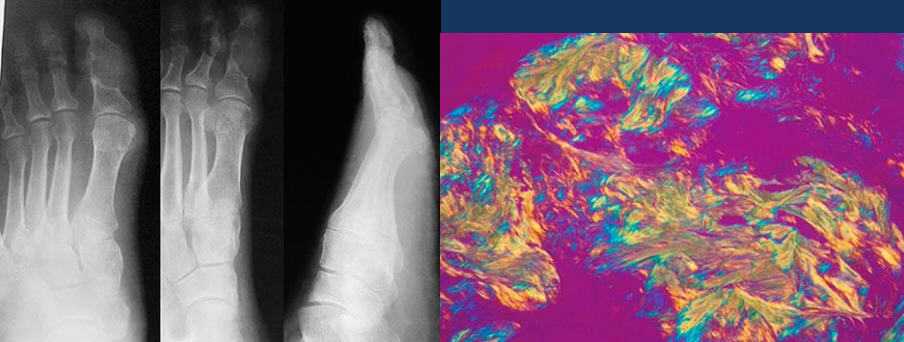

gout

pseudogout = pos birefringent